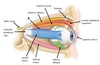

Name muscles A and B

A - Superior oblique

B - Inferior oblique

Name structures A and B

A - Common tendinous ring

B - Trochlea